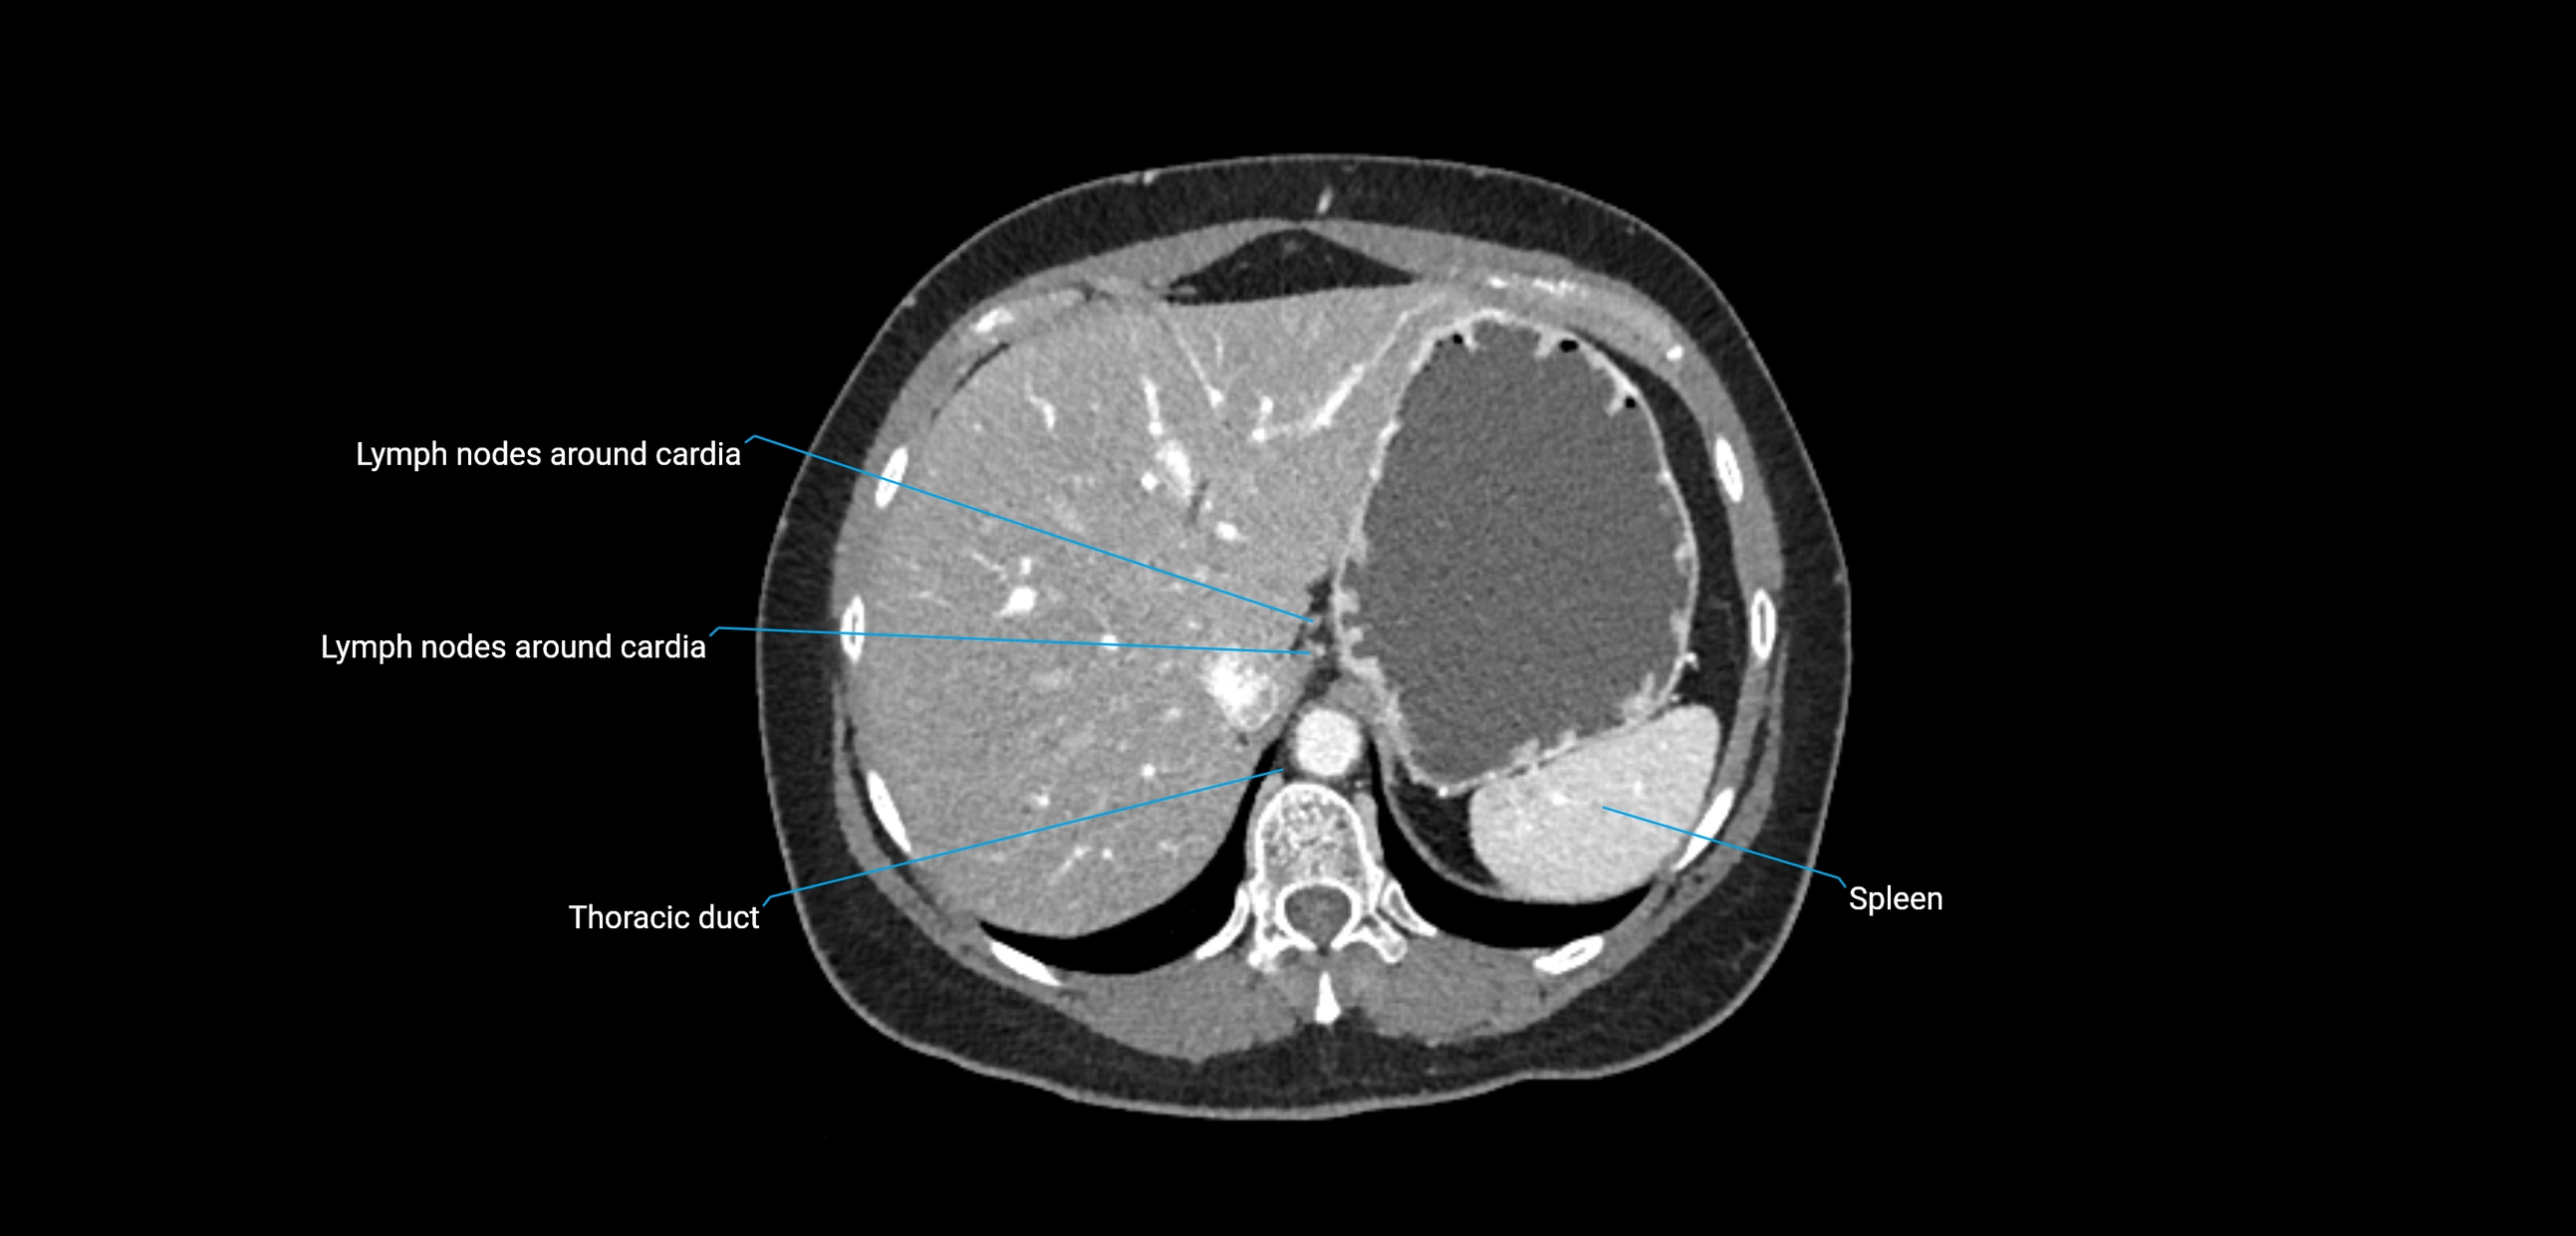

These nodes receive lymph from a wide range of abdominal and pelvic structures. Specifically, they drain lymph from the kidneys, suprarenal glands, gonads (testes/ovaries), uterus, uterine tubes, and pelvic organs, before converging into the lumbar lymphatic trunks, which terminate in the cisterna chyli → thoracic duct.

• Drain lymph from the kidneys, suprarenal glands, ureters, gonads, and pelvic organs

• Provide a major pathway to the cisterna chyli and thoracic duct

CT image

image